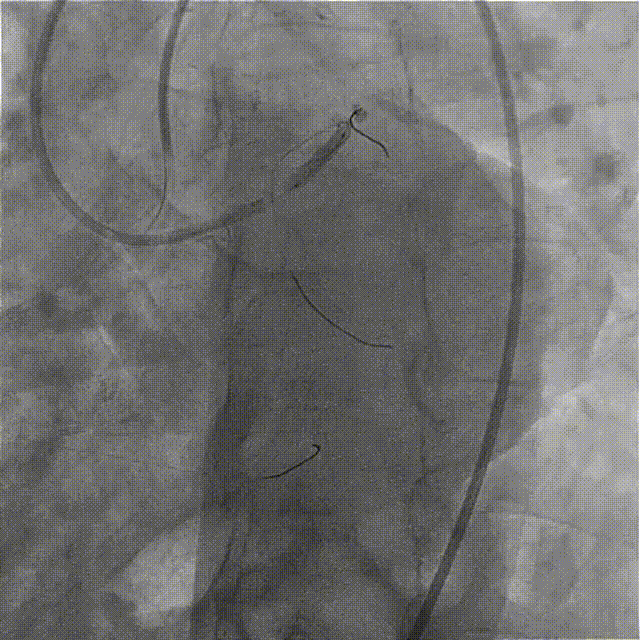

在HighTrack微导管的支撑下及逆向导丝的指引下,正向用Gaia First、Gaia Third、PILOT 200导丝反复尝试,均未能通过闭塞段进入血管真腔。

逆向重新送入一根SION Blue导丝反复尝试,最终进入正向指引导管内,推送逆向微导管至正向指引导管内,逆向送入RG3导丝至正向入口,正向沿RG3导丝推送微导管至LAD远段,撤出逆向导丝及微导管,交换一根SION Blue导丝至LAD远段。